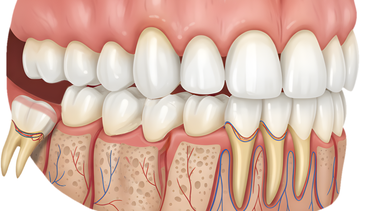

Viêm lợi trùm do hướng mọc răng khôn

Răng khôn là chiếc răng mọc cuối cùng nên thường không còn đủ chỗ để mọc đúng hướng. Vì vậy, nhiều người gặp tình trạng răng khôn mọc lệch, mọc nghiêng, thậm chí mọc ngầm trong nướu. Khi răng mọc sai hướng, lợi phía trên không thể mở ra hoàn toàn, dễ trùm lên răng và tích tụ vi khuẩn. Vùng lợi này khó được làm sạch, dẫn đến sưng đau, viêm nhiễm kéo dài và gây khó chịu trong sinh hoạt hằng ngày.